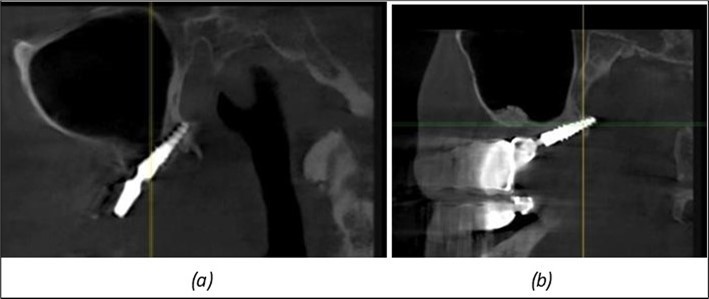

Figure 11.Implants in the anterior area anchored in the nasal cortex (BCS and TPG): (a), (c) – BCS implants fixed in the nasal cortex; (b), (d) – TPG implants fixed in the second nasal cortex with compression in the trabecular area.